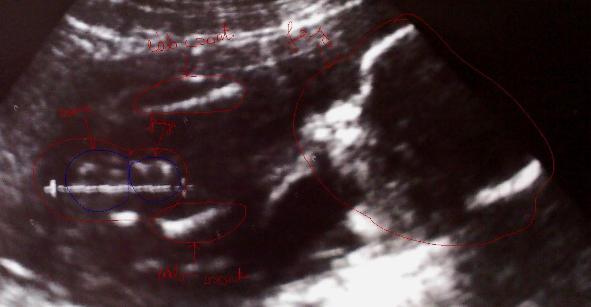

akkor jönnek képek:

Mikor még fiú volt, és hozzá az akkori magyarázat: Kép

Itt pedig már lány: Kép

Kép magyarázat: jobbra a nagy kör a feje, bal oldalon alul és felül van egy-egy fehér csík az a csont a lábában és a két csont között volt akkor a lényeg amit a doki azzal a vonnallal jelölt meg, a kisebbik kék körre a fütyit mondta a nagyobbikra a zacsit! Én akkor ezt így el is tudtam képzelni, ma már nem tudom akkor mi volt ott :lol: :lol: Nekem a második képen is az bármi lehet, a doki szerint punci!! Én már tényleg csak azt fogom elhinni amit a kezmben tartok majd!! :?

A fejfájás simán lehet a kialvatlanság miatt. Próbálj meg többet aludni. Úgy tudom, az algopiynt szedhetjük. A képekből én se tudtam rendesen kivenni, amit kell. Kicsit furának tartom, hogy olyan nagy legyen a zacsija. A baba méretéhezhez képest. :lol: A 4D-n mit mondtak? Mert ott jobban látszik minden. Bocs, tudom már kérdeztem, de szita az agyam.

Ági 4D-n sem látszott semmi! A második kép akkor 4D-n voltunk de nem tudta áttenni 4D-be mert semmi sem látszott, hogy miért azt nem tudom nem értek hozzá sajnos, de még az arcát sem láttuk 4D-ben! Az egész nem ért semmit csak felesleges pénzkidobás volt. Sem a lábát sem a kezét semmit! Most vagy nem jó helyen voltunk vagy a Mi Babácskánk ennyire rafinált, már nem tudom!!! A zacsit nem tudom ez nem nagyon jó kép mert amiről a képet csináltam azon élesebben látszódik minden, azon nem tűnik nagynak a babához képest mert a vonal amit a doki odatett az kicsit zavaró! Na de kár is ezen rágódni, 8 hét és mindenre fény derül, csak most nem tudok a neveken dűlőre jutni! Nem tudok egyszerűen ráhangolódni a lánynevekre!!! :roll: :roll:

Az elsö képen én nem nagyon tudok kivenni sokmindent, de a 2. nagyon nunis kinézetü. :)